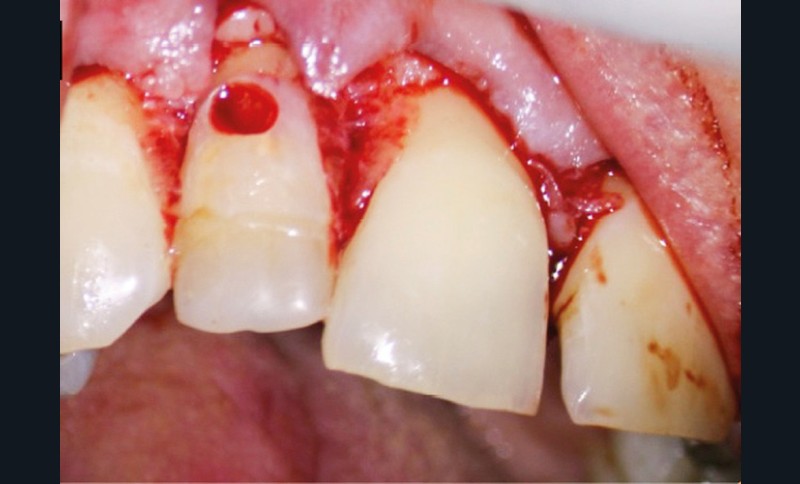

10. réalisation d’un lambeau, en commençant par l’incision intra-sulculaire à l’aide d’une lame de bistouri n° 15C, s’étendant de deux dents en mésial et distal de la dent perforée (de manière à avoir une laxité suffisante pour exposer aisément la zone de perforation – accès visuel et instrumental) ;

11. décollement du lambeau (décolleur de Molt) : décoller les papilles dans un premier temps, puis la gencive kératinisée en pleine épaisseur de sorte à éviter de déchirer le lambeau ;

12. une légère ostéotomie peut être réalisée afin de permettre une bonne isolation et/ou pour respecter l’espace biologique ;

13. si possible, mise en place d’un champ opératoire sur la dent concernée, de sorte à isoler la zone de perforation de toute humidité (fig. 2) ;